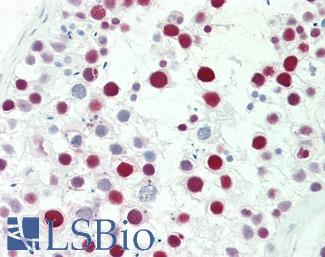

Estrogen Receptor / ESR1

Anti-ER Alpha / Estrogen Receptor antibody IHC staining of human breast. Immunohistochemistry of formalin-fixed, paraffin-embedded tissue after heat-induced antigen retrieval. Antibody LS-B10527 dilution 1:100.